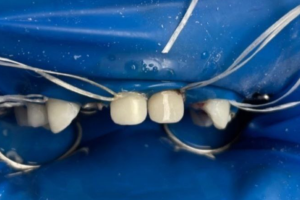

Семейная областная стоматология "Кидди Дентал" - это команда компетентных врачей, каждый из которых знает и любит свое дело. Опыт наших врачей, использование современного оборудования и надежных материалов позволят проводить лечение любой сложности.